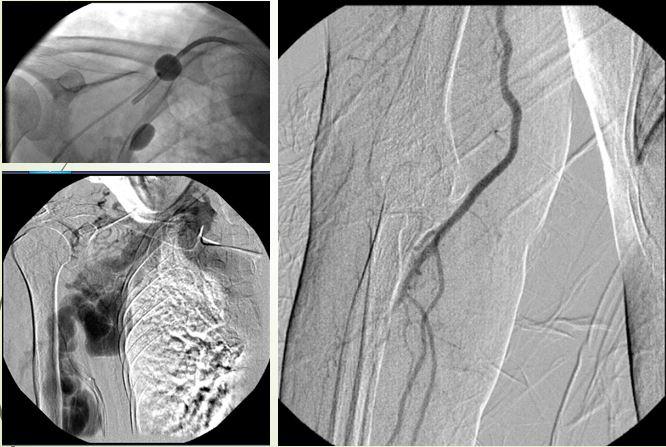

Chọc thẳng vào động mạch cảnh để thả bóng, bít rò động mạch xoang hang

Sau tai nạn giao thông, bệnh nhân nam 34 tuổi bị đỏ mắt, lồi mắt, được chẩn đoán rò động mạch xoang hang và điều trị bằng phương pháp cổ điển là mổ động mạch cảnh, thả miếng cơ để bít lỗ rò.

H. Bệnh nhân nam 34 tuổi bị rò động mạch xoang hang sau tai nạn giao thông, tái phát sau mổ thả cơ và cột động mạch cảnh năm 2004

Phương pháp thả cơ được thực hiện khoảng năm 2007 trở về trước trong thời gian rất dài, vì các trường hợp rò động mạch xoang hang do tai nạn giao thông ở nước ta xảy ra rất nhiều, sau điều trị có trường hợp thành công, có trường hợp tái phát. Đây là trường hợp tái phát do phát sinh tuần hoàn bàng hệ, bệnh nhân vẫn còn đỏ mắt, lồi mắt. BS Cường cho biết tại thời điẻm 2004 cả nước gom lại chắc chưa được 10 cái coil, can thiệp đặt coil bệnh nhân sẽ tốn rất nhiều tiền.

Các bác sĩ có quyết định khá mạo hiểm là chọc trực tiếp vào động mạch cảnh ở cổ, sau đó can thiệp đặt bóng.

Ca can thiệp này khiến các bác sĩ vất vả vì phải ép động mạch cảnh suốt 1 giờ đồng hồ, đồng thời có bác sĩ tai mũi họng đứng bên cạnh, đề phòng tình huống phải mở khí quản.

Sau can thiệp, bệnh nhân đã được điều trị hiệu quả, sau can thiệp không để lại sẹo vết đáng kể.